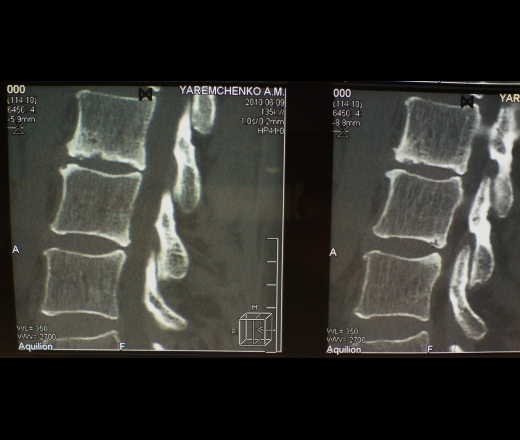

Коллеги, добрый вечер. Вот такой случай. Женщина 50 лет обратилась на КТ с подозрением на спондилит L2-3( по р-снимкам). Боли беспокоят давно. Работа сопровождалась физ трудом с периодическии травмами. После того, как 1 год назад упала на лестнице(правда удалось устоять на ногах, но было резкое переразгибание спины) боли усилились. На КТ поставили спондилит... женщину консультировали все, включая туб диспанцер. диагноз спондилит оставили. НО! кровь абсолютно спокойна и резкого острого начала болезни не было. пропила курс антибиотиков - то ли лучше то ли нет- понять не может. Мне видется дегенеративный процесс по типу остеохондроза как исход ее "работящей" жизни... Какие ваши мнения?

Последствия спондилодисцита, дегенеративные изменения. Аксиалов кортикалов нет? и области диска. На основании чего ставят спондилит? МРТ (чисто случайно) не делали?

Банальный остеохондроз с букетом изменений замыкательных пластин и вторичными изменениями в позвонке L2, все изменения приобретенные за длительный срок. Данныз за спондилит, да и за спондилодисцит, по моему мнению, нет.

С уважением, С.Н. Нагорный

Вывод следующий - остеохондроз это не только изменения фиброзного кольца, ведь не только из его одного диск состоит, это и изменения замыкательных пластин, это и изменения структуры сопредельных позвонков, иначе я процесс не представляю. Но, как мне кажется, однозначно оспаривать последствия ПЕРЕНЕСЕНОГО ранее спондилодисцита тоже нельзя. И еще, как версия...а почему бы спондилодисциту и не быть хроническим!!!!

Данных за спондилит-дисцит не выявлено.